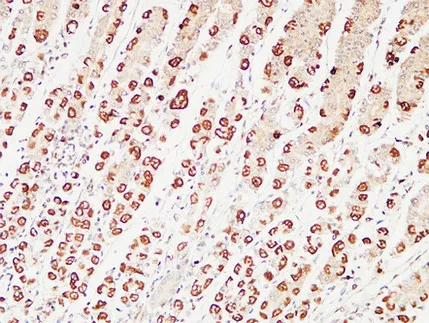

KiSS-1R Rabbit Polyclonal Antibody

Cat: APRab13039